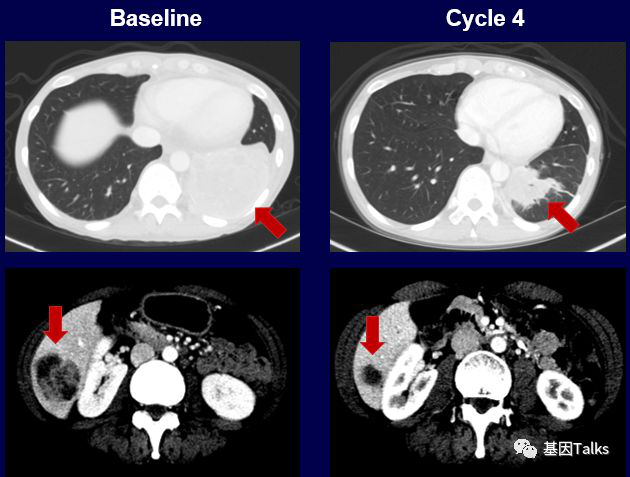

三个不同癌种不同融合的案例:

(1)1例肺癌合并SQSTM1-NTRK1融合:

(2)1例婴儿纤维肉瘤合并ETV6-NTRK3融合:

(3)1例分泌性乳腺癌合并ETV6-NTRK3融合:

上图下半部分显示治疗2周后,新发的耐药突变位点G595R已经检测不到,到现在治疗已经6个月了,治疗效果依然很好,未见有新的耐药位点出现。LOXO-195已经被FDA批准正式召开临床试验,耐药患者有了新希望。